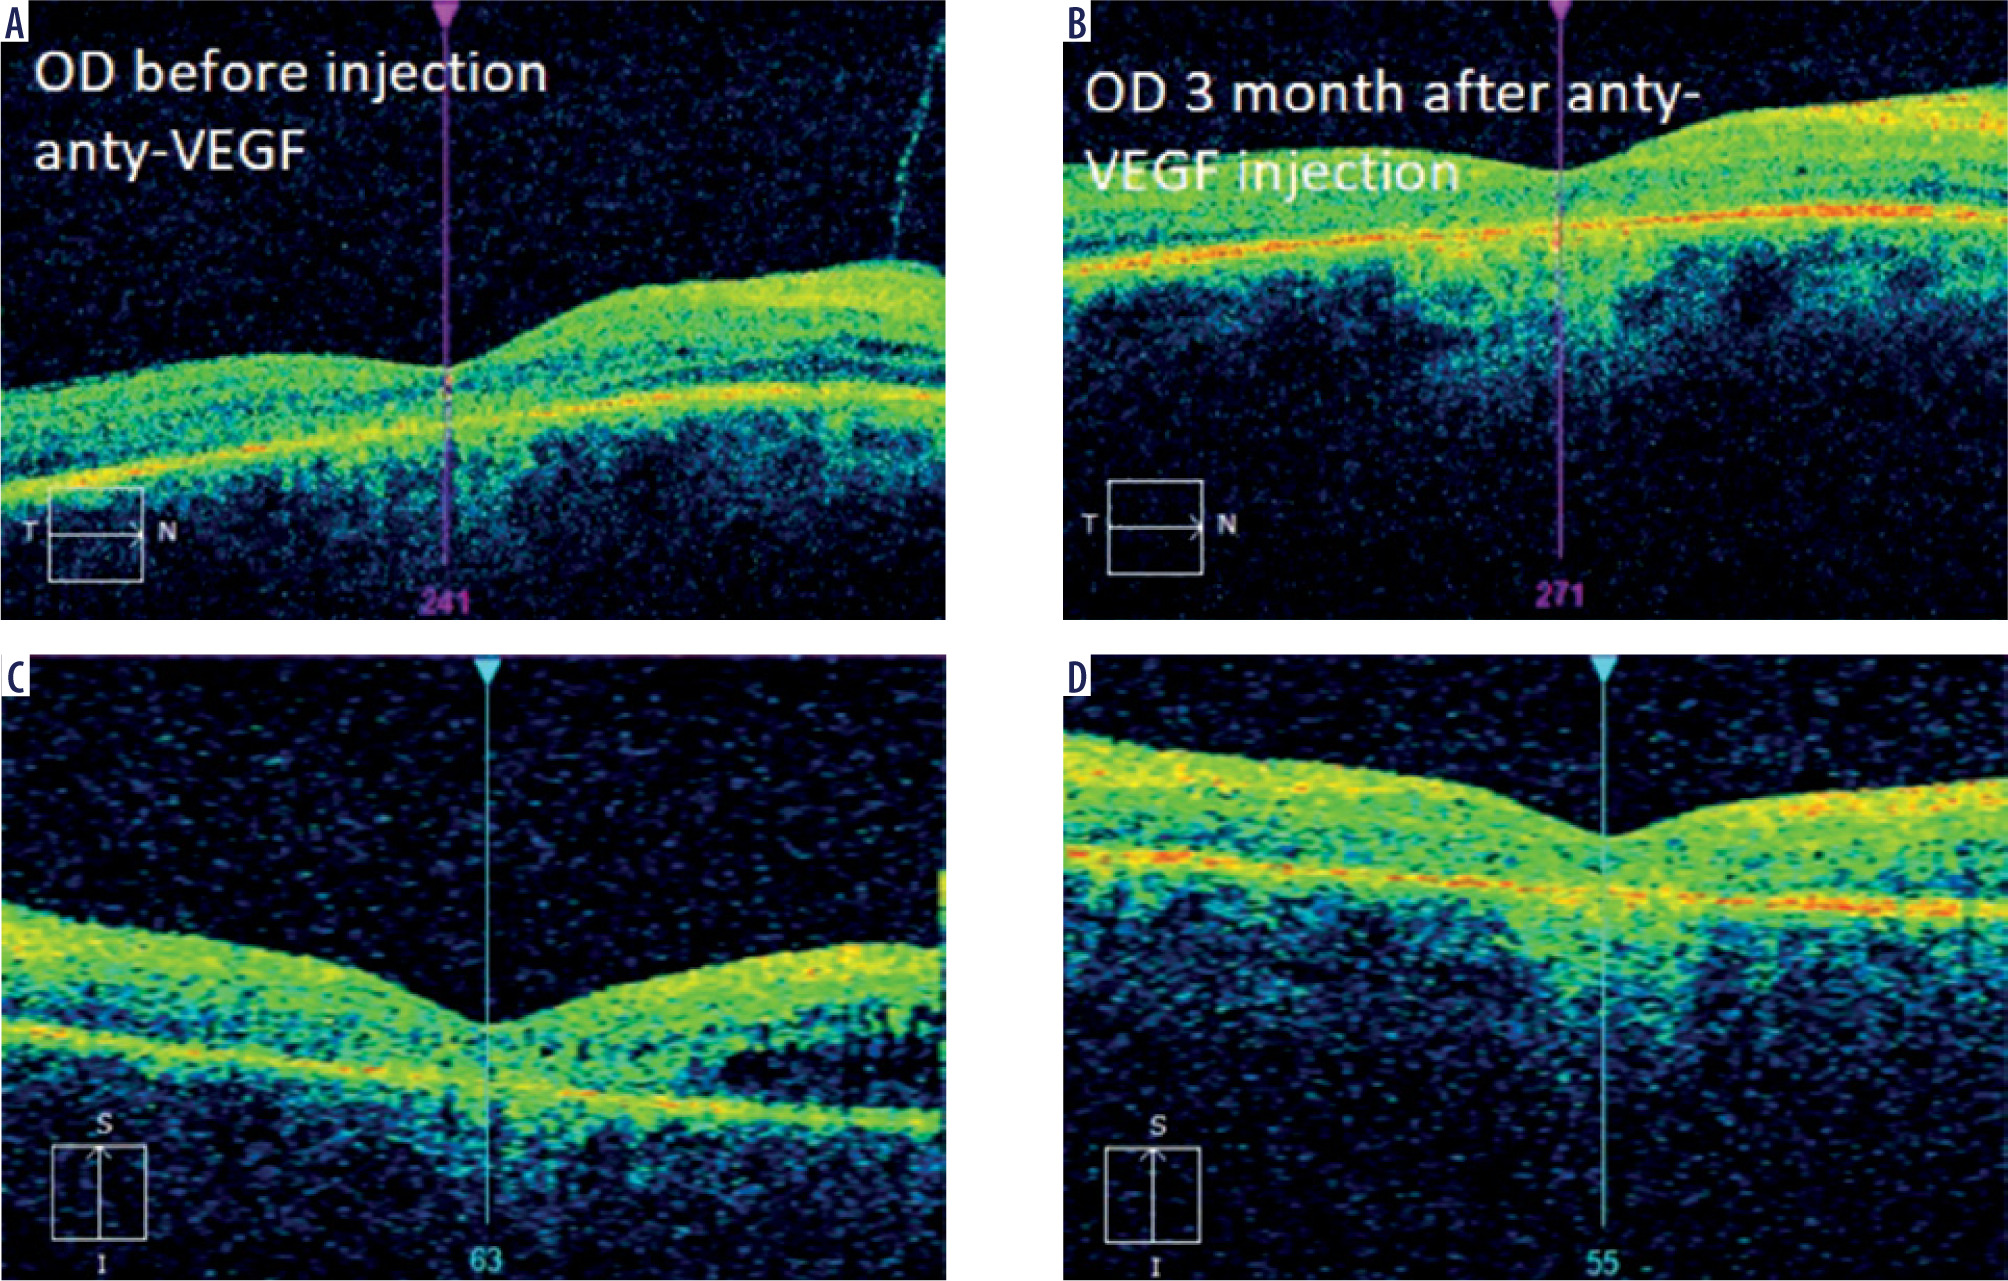

Intravitreal anti-VEGF drugs are another treatment option for CME in patients with RP. The efficacy of these therapies has varied depending on the study and medications used. In 2006, Melo et al. evaluated the effect of bevacizumab (Avastin) in 2 patients with CME associated with RP. In the conclusion of their study, bevacizumab was found to be ineffective in treating this complication [20]. In 2009, Artunay et al. published the results of a study of 7 patients in whom a single dose of ranibizumab had no statistically significant effect on CMT compared to a control group at 6-month follow-up evaluation [21]. In 2016, Strong et al. presented an interesting case of a patient with RP and concomitant CME in whom there was a reduction in CMT after two injections of aflibercept despite a previous minimal response to intravitreal ranibizumab [22]. The same author in 2020 confirmed in his subsequent prospective study that aflibercept may have a favorable impact on CMT in up to 37.9% of patients [14]. Of note, despite demonstration of an anatomic response, no statistically significant improvement in best-corrected visual acuity was observed. These observations are in line with our experience, where CMT reduction was not associated with VA improvement (Figure 2).